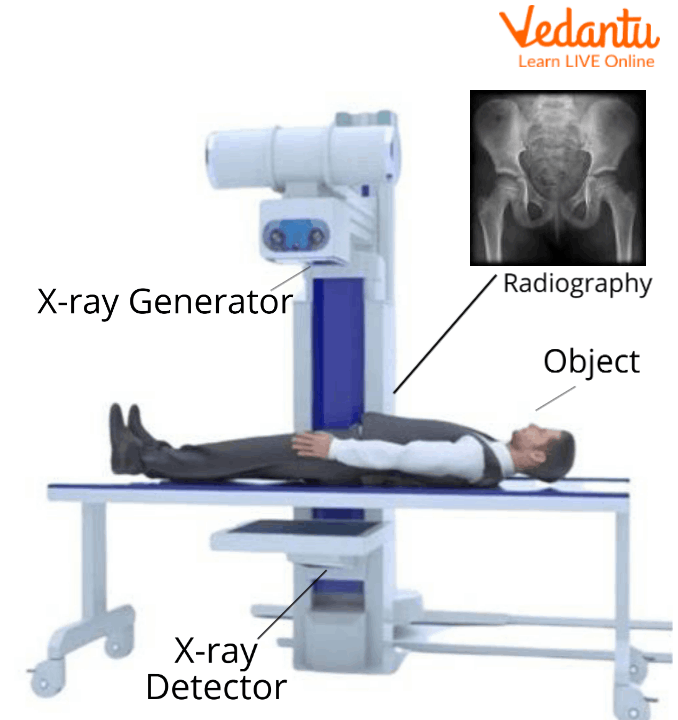

How Do X-rays Work?

X-rays are produced when electrons of high velocity come to collide with the metal plates. During this process, they give out energy as x-rays and themselves are absorbed by the metal plate.

Firstly, the person is laid on an x-ray machine. The x-ray beam travels through the air and it comes in contact with the tissues of the body and then it produces an image on a metal film.

X-ray Machine

Soft tissues of the body like organs and skin cannot absorb the high velocity rays and the beam passes through them.

There are dense materials present inside our body for example bones, they can absorb the radiations of x-rays.

In the areas which are exposed to x-rays, they develop a film called x-rays film. White areas in the film show denser regions of the body for example bones which absorb x-rays and black areas on an x-ray show the soft tissues from which x-rays have not passed.